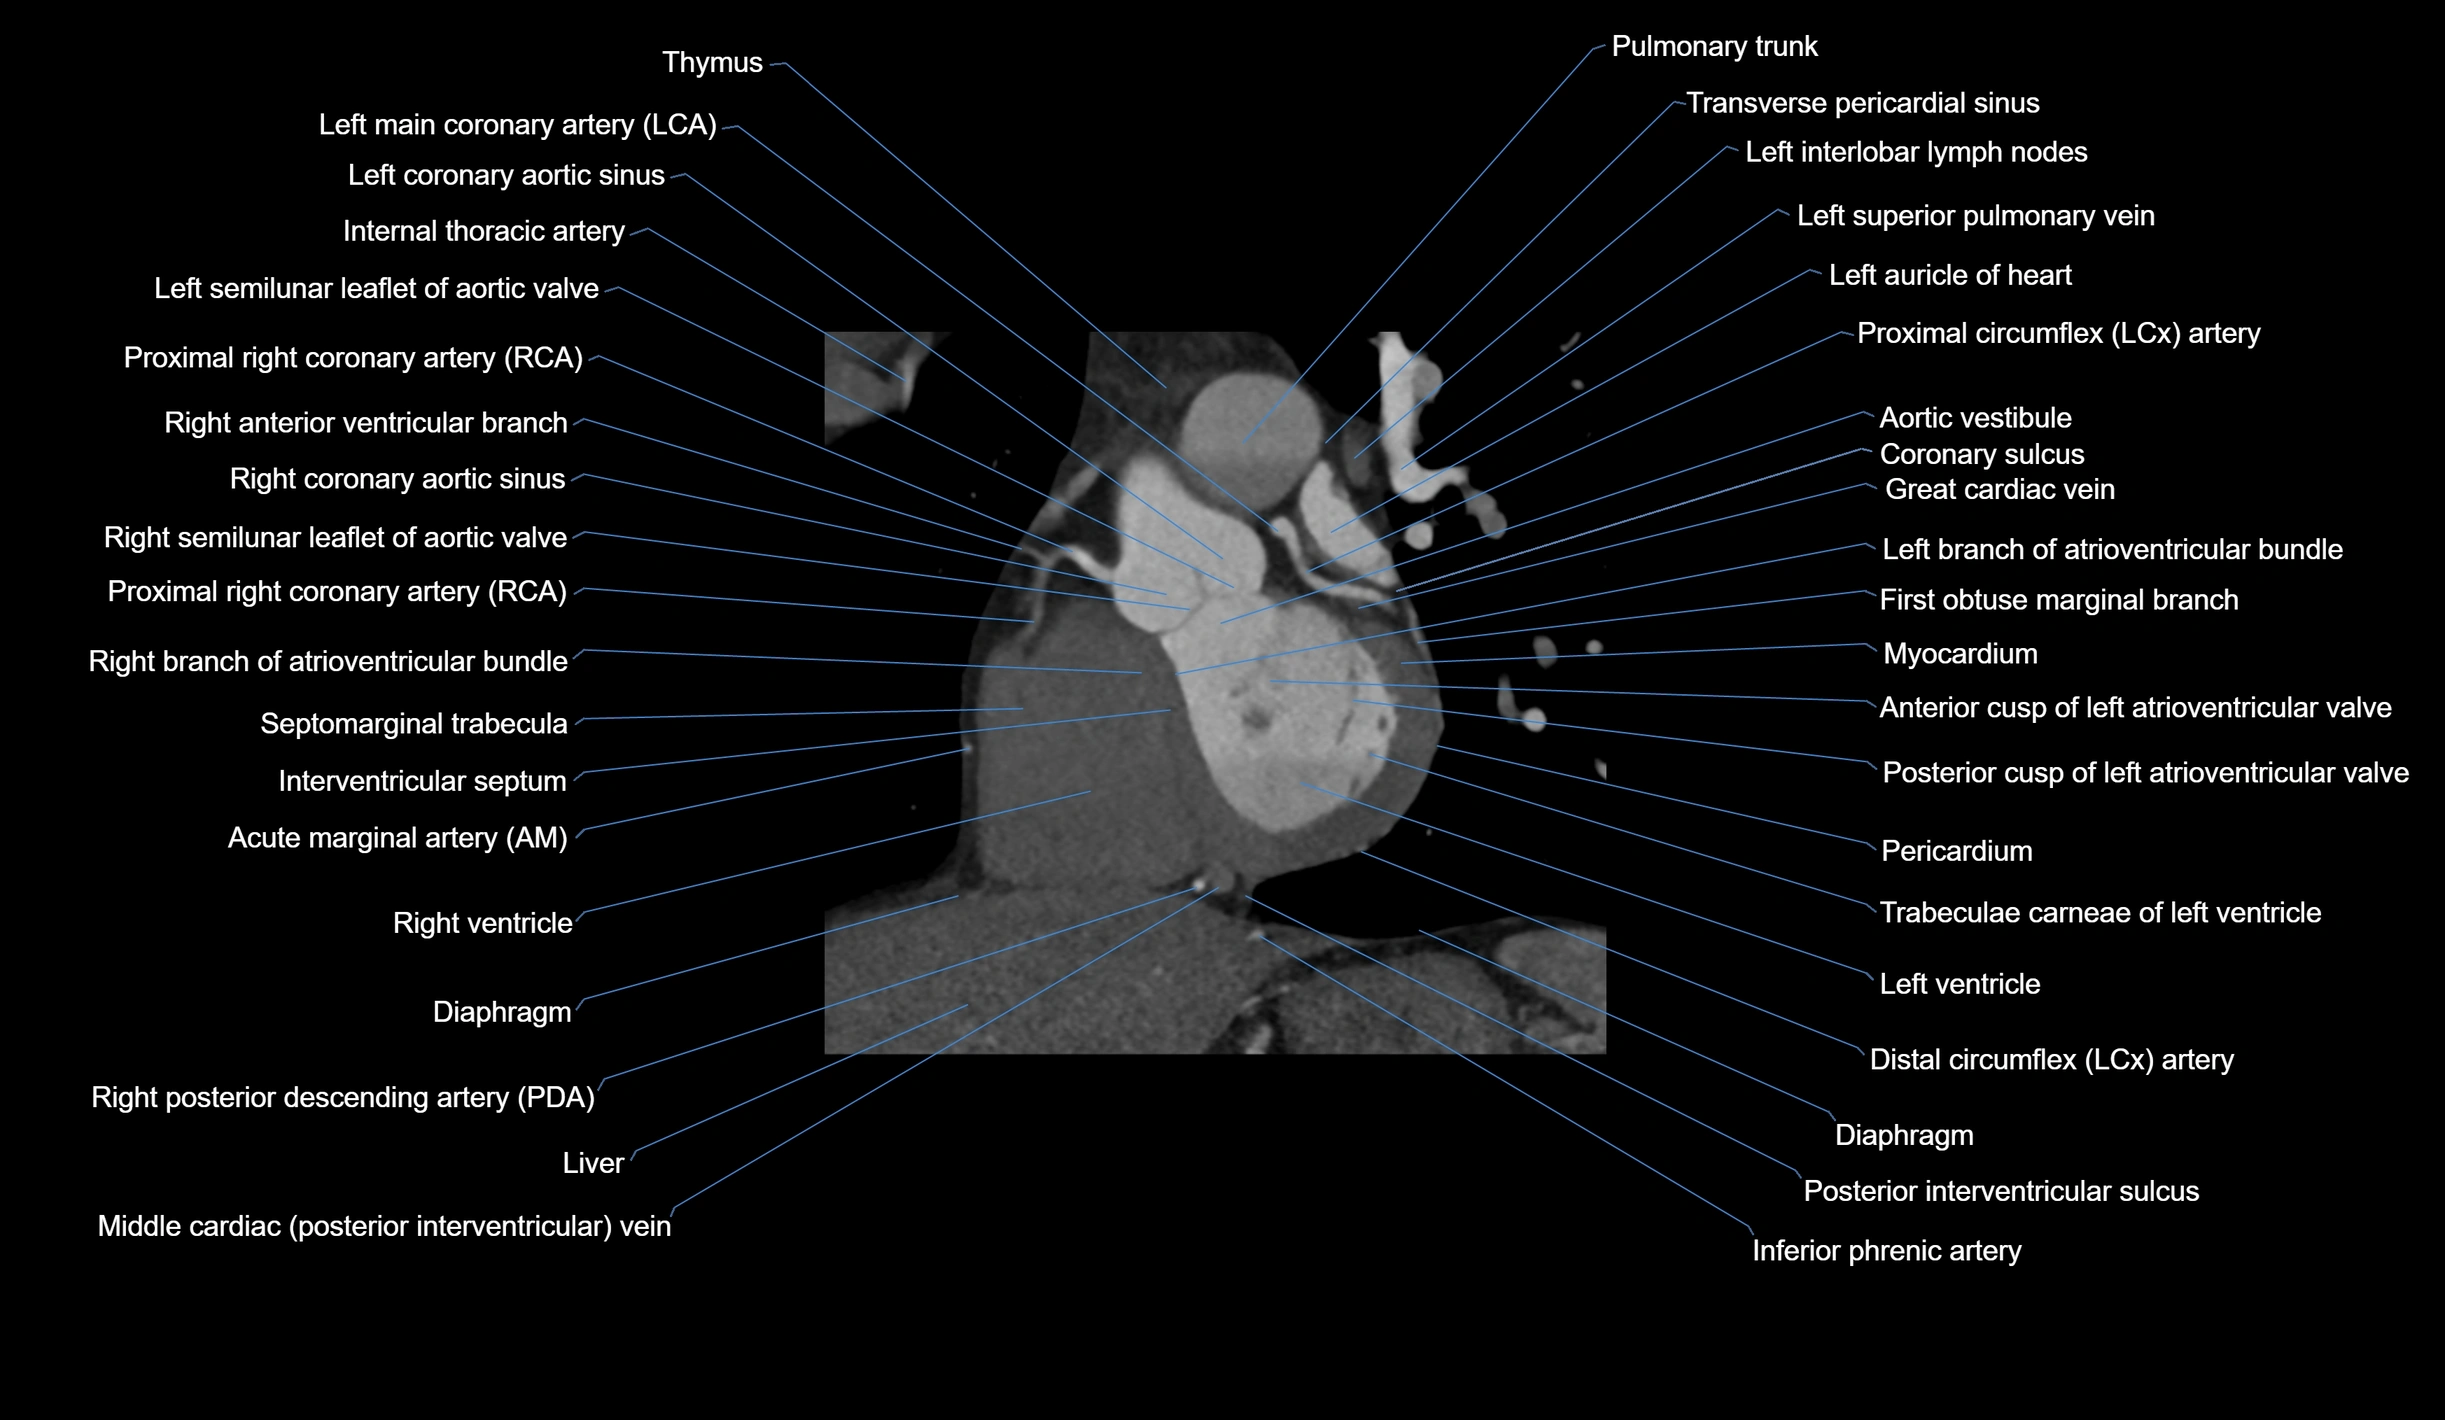

CT Appearance

Non-contrast CT (Calcium Scoring):

-

AM artery visualized for coronary calcium scoring

Calcified plaques appear as hyperdense foci; scored with Agatston method

CT Coronary Angiography (CCTA):

Best non-invasive modality for acute marginal artery visualization

Shows origin, course along the acute margin, and right ventricular branches

Detects stenosis, occlusion, calcified and non-calcified plaques, aneurysm, or anomalous course

Multiplanar reformats and 3D reconstructions help in pre-PCI and surgical planning

Critical for assessing right ventricular infarction risk in RCA disease

MRI image

CT images